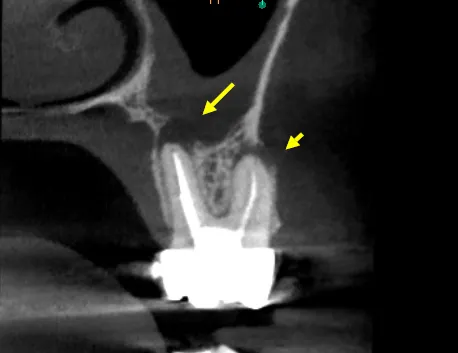

Severely calcified MB2 canal not located during initial treatment—CBCT showed complete sclerosis

The referring dentist had completed what appeared to be adequate endodontic treatment two years prior, but the patient continued to experience intermittent discomfort and sensitivity to percussion. Clinical examination revealed no obvious defects, but CBCT imaging told a different story: a completely calcified MB2 canal with associated periapical pathology.

Calcification of this severity requires a systematic approach. We used CBCT data to precisely locate the canal orifice, then employed ultrasonic tips to create a troughing pathway through the sclerotic dentin. Micro-openers (size 06 and 08) were used to negotiate the calcified canal under high magnification.

• CBCT Analysis: Identified exact MB2 location and depth of calcification

The entire procedure took approximately 2 hours. The canal was successfully negotiated to full working length, cleaned with GentleWave technology, and obturated along with the other three canals.